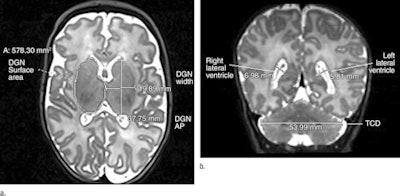

Walsh and colleagues performed MRI exams on 199 moderate and late preterm infants and 50 infants born between 38 and 44 weeks of gestation (control group), looking for signs of brain injury. They also compared the size and maturation of multiple brain structures between the two groups (Radiology, June 10, 2014).

Injury rates were similar between the two cohorts; however, moderate and late preterm birth was associated with smaller brain size at term-equivalent age, the researchers found. In addition, moderate and late preterm infants had less developed myelination in one part of the brain and more immature gyral folding than the control group.